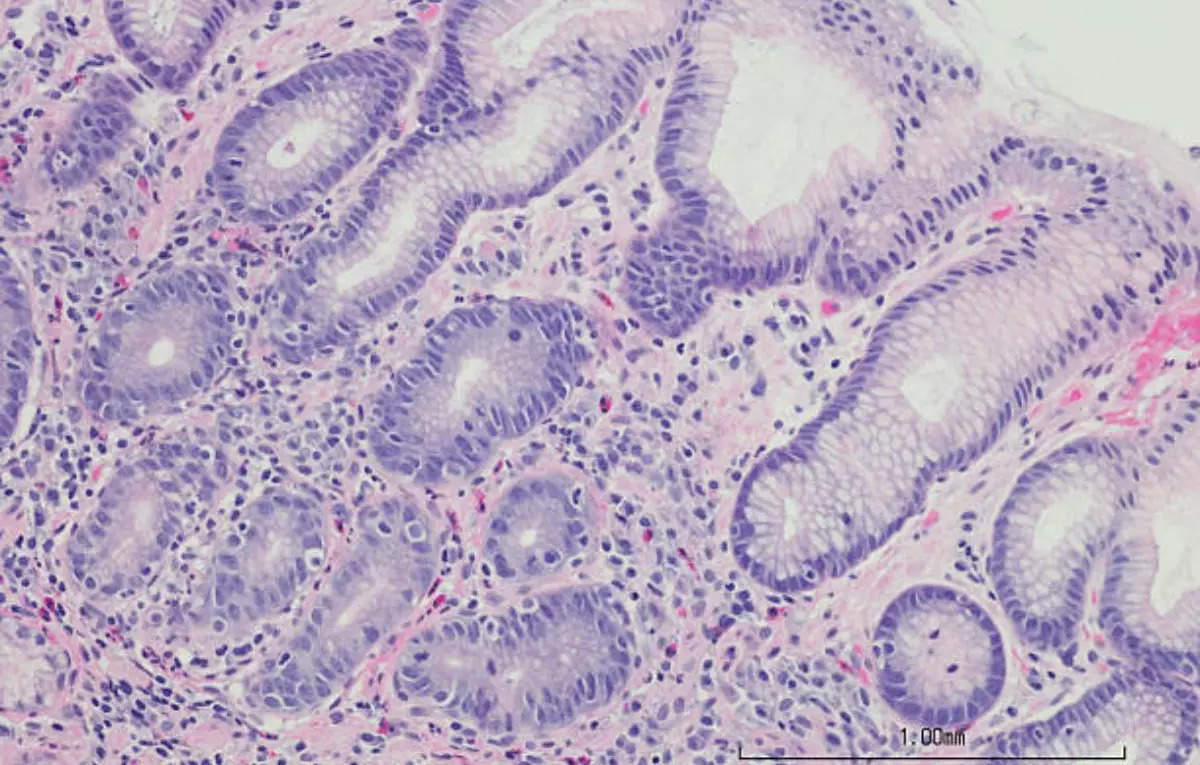

Severe infection with Helicobacter pylori can result in ulcers and stomach cancer. Annually, there are over 1.2 million new cases of stomach cancer, causing 8,65,000 deaths worldwide. Eliminating Helicobacter pylori infection is difficult due to its alarming levels of antibiotic resistance. The WHO has classified it as a ‘high priority’ condition, stressing the urgent requirement for new therapies.